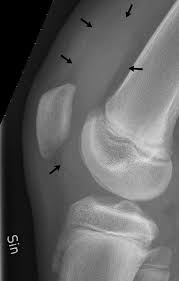

- علامة رضفة النقر (Patellar Tap): تُستخدم للانصبابات المتوسطة إلى الكبيرة، حيث يتم ضغط الجراب فوق الرضفة (Suprapatellar pouch) والنقر على الرضفة لملاحظة ارتدادها عن عظم الفخذ .

3.2 التصوير التشخيصي

أ. التصوير بالموجات فوق الصوتية (Ultrasound)

يعتبر التصوير بالأمواج فوق الصوتية أداة ممتازة لتقييم الانصبابات المفصلية، حيث يتميز :

- حساسية عالية: يمكنه اكتشاف كميات صغيرة من السائل (أقل من 1 مل).

- التوجيه الإجرائي: يُستخدم لتوجيه إبرة بزل المفصل بدقة، مما يزيد من نسبة النجاح ويقلل المضاعفات.

- التكلفة المنخفضة: متوفر وغير مكلف نسبياً.